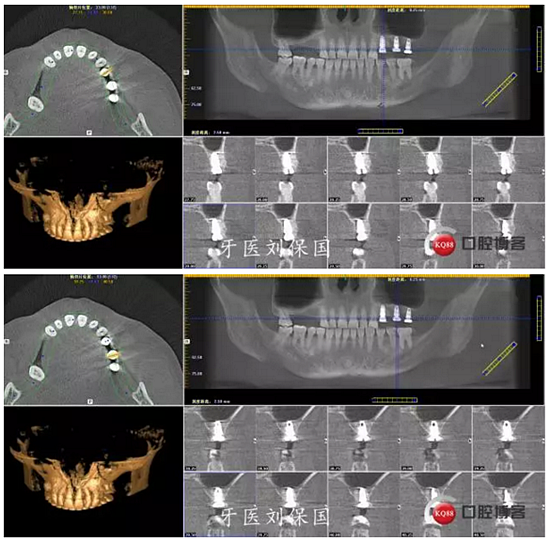

3.術(shù)后CT:

4.六個月后二期CT: